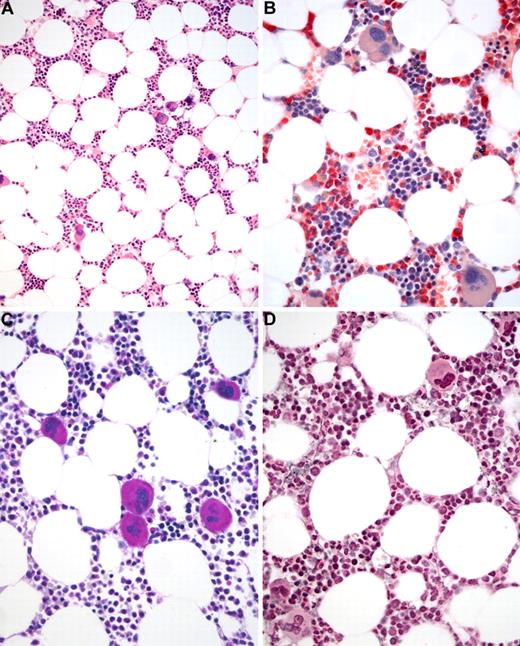

BM biopsy histology in ET in overview (×70) and low-power (×210) field. (A) Survey with hematoxylin and eosin-stained section shows an age-matched cellularity but prominent large to giant mature megakaryocytes in random distribution or loose clusters. (B) Chloroacetate esterase reaction demonstrates a normal amount and distribution of neutrophil granulopoiesis (red) and erythropoiesis besides the prominent megakaryocytes. (C) PAS staining reveals a hyperlobulation of megakaryocyte nuclei (almost staghorn-like) and mature cytoplasm without evidence of significant abnormalities. (D) Reticulin stain discloses no increase in fibers but large megakaryocytes. Images were acquired using Zeiss Axioplan 2, 10×/0.50 and 20×/0.50 EC PlanNeofluar.

BM biopsy histology in ET in overview (×70) and low-power (×210) field. (A) Survey with hematoxylin and eosin-stained section shows an age-matched cellularity but prominent large to giant mature megakaryocytes in random distribution or loose clusters. (B) Chloroacetate esterase reaction demonstrates a normal amount and distribution of neutrophil granulopoiesis (red) and erythropoiesis besides the prominent megakaryocytes. (C) PAS staining reveals a hyperlobulation of megakaryocyte nuclei (almost staghorn-like) and mature cytoplasm without evidence of significant abnormalities. (D) Reticulin stain discloses no increase in fibers but large megakaryocytes. Images were acquired using Zeiss Axioplan 2, 10×/0.50 and 20×/0.50 EC PlanNeofluar.